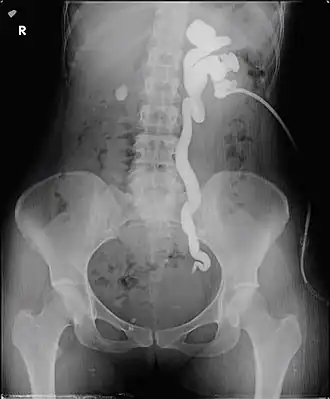

Antegrade pyelography, anterograde pyelography

Antegrade pyelogram of grade III hydronephrosis with obstruction at the ureterovesical junction due to bladder endometriosis in a 29 year old female. The tip of the nephrostomy is located in an inferior calyx.

Antegrade pyelography is the procedure used to visualize the upper collecting system of the urinary tract, i.e., kidney and ureter. It is done in cases where excretory or retrograde pyelography has failed or contraindicated, or when a nephrostomy tube is in place or delineation of upper tract is desired. It is commonly used to diagnose upper tract obstruction, hydronephrosis, and ureteropelvic junction obstruction. In this, radiocontrast dye is injected into the renal pelvis and X-rays are taken. It provides detailed anatomy of the upper collecting system. As it is an invasive procedure, it is chosen when other non-invasive tests are non confirmatory or contraindicated and patient monitoring is required prior and after the procedure.[11][12]